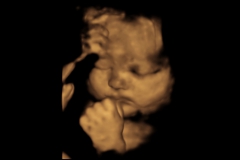

Ultrasound images